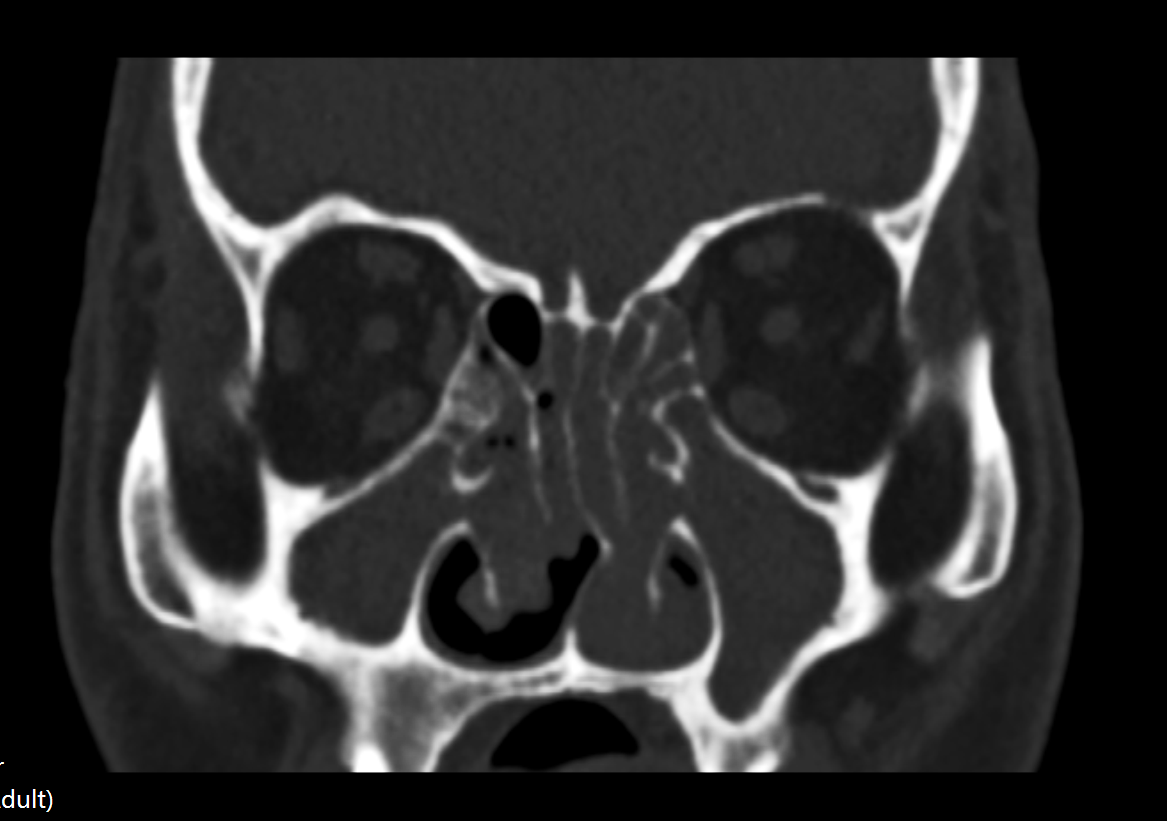

我院鼻科主任李明栋在查体、问诊后,详细为其进行了检查。李主任介绍说,患者现在鼻腔、鼻窦长满了息肉,可以说整个鼻子被息肉填满了,这也是他不能呼吸的主要原因。而造成鼻息肉的原因是多年鼻窦炎诱发的。所以,这次不光要解决他的鼻息肉问题,还要解决根本的鼻窦炎问题,标本兼治,才能解决根本问题。

鼻窦炎可能诱发鼻息肉,这是因为鼻窦炎患者的鼻腔粘膜反复水肿,大量脓性鼻涕的刺激,可以肉发钩突、中鼻道以及下鼻甲等部位粘膜高度水肿,久而久之,可发生息肉样变,并逐渐增大,从而形成鼻息肉。